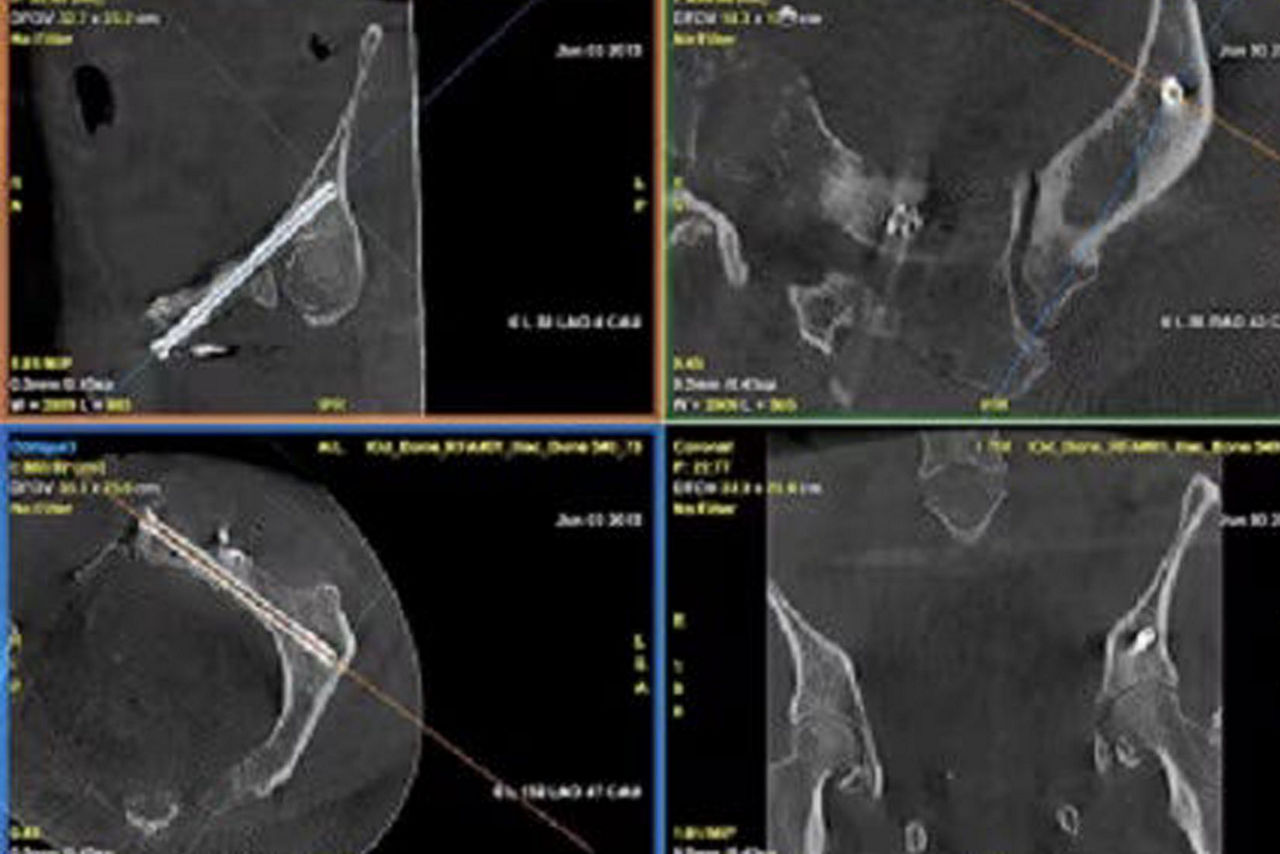

Real-time visualization

Provide real-time visualization of needle positions in the 3D space

Improve outcomes

Helps improve accuracy and reduce dose during needle interventions